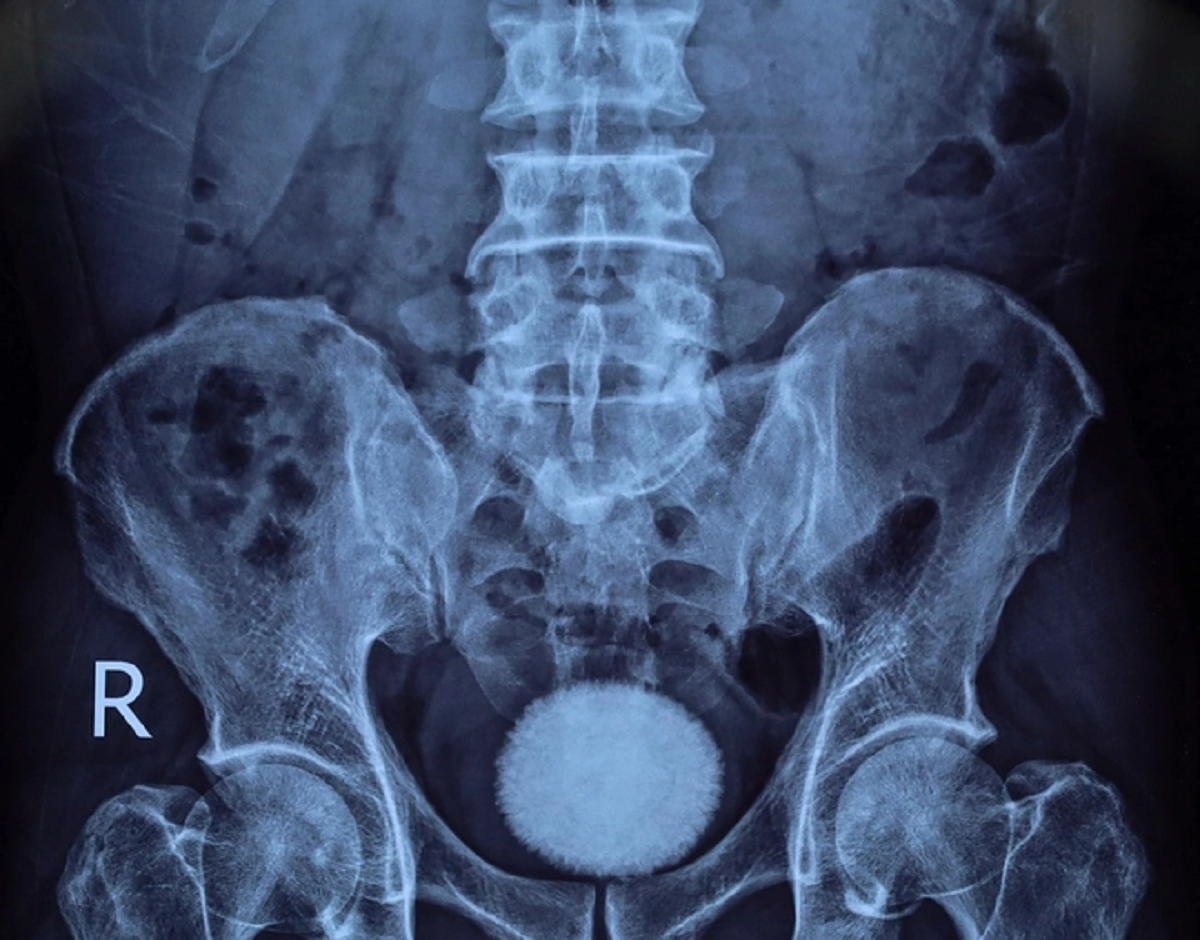

Khai thác tiền sử bệnh trước đó, bệnh nhân đến khám trong tình trạng tiểu buốt, tiểu khó kéo dài, kèm đau vùng hạ vị. Qua thăm khám lâm sàng, siêu âm và chụp X-quang, các bác sĩ phát hiện trong bàng quang có viên sỏi kích thước khoảng 60x40 mm.

Nhận định đây là viên sỏi lớn, nguy cơ gây tắc nghẽn và nhiễm trùng đường tiết niệu, ê kíp bác sĩ đã chỉ định phẫu thuật mở lấy sỏi bàng quang.

Trong quá trình phẫu thuật, các bác sĩ rạch da đường giữa trên xương mu, tiếp cận bàng quang và lấy ra một viên sỏi lớn, kích thước tương đương quả trứng ngỗng. Sau khi lấy sỏi, bàng quang được bơm rửa sạch và khâu phục hồi theo đúng quy trình chuyên môn. Ca mổ diễn ra thuận lợi. Hiện bệnh nhân tỉnh táo, sức khỏe ổn định và đang được theo dõi, chăm sóc hậu phẫu.